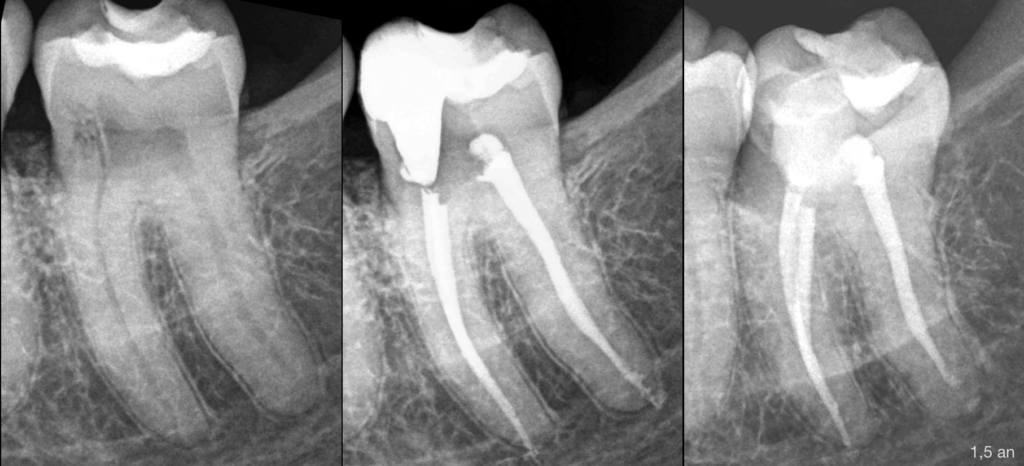

🔍 Pulpe normale, os péri apical normal

Résorption radiculaire externe cervicale inflammatoire

Traitement canalaire

Traitement de la résorption (curetage, restauration)